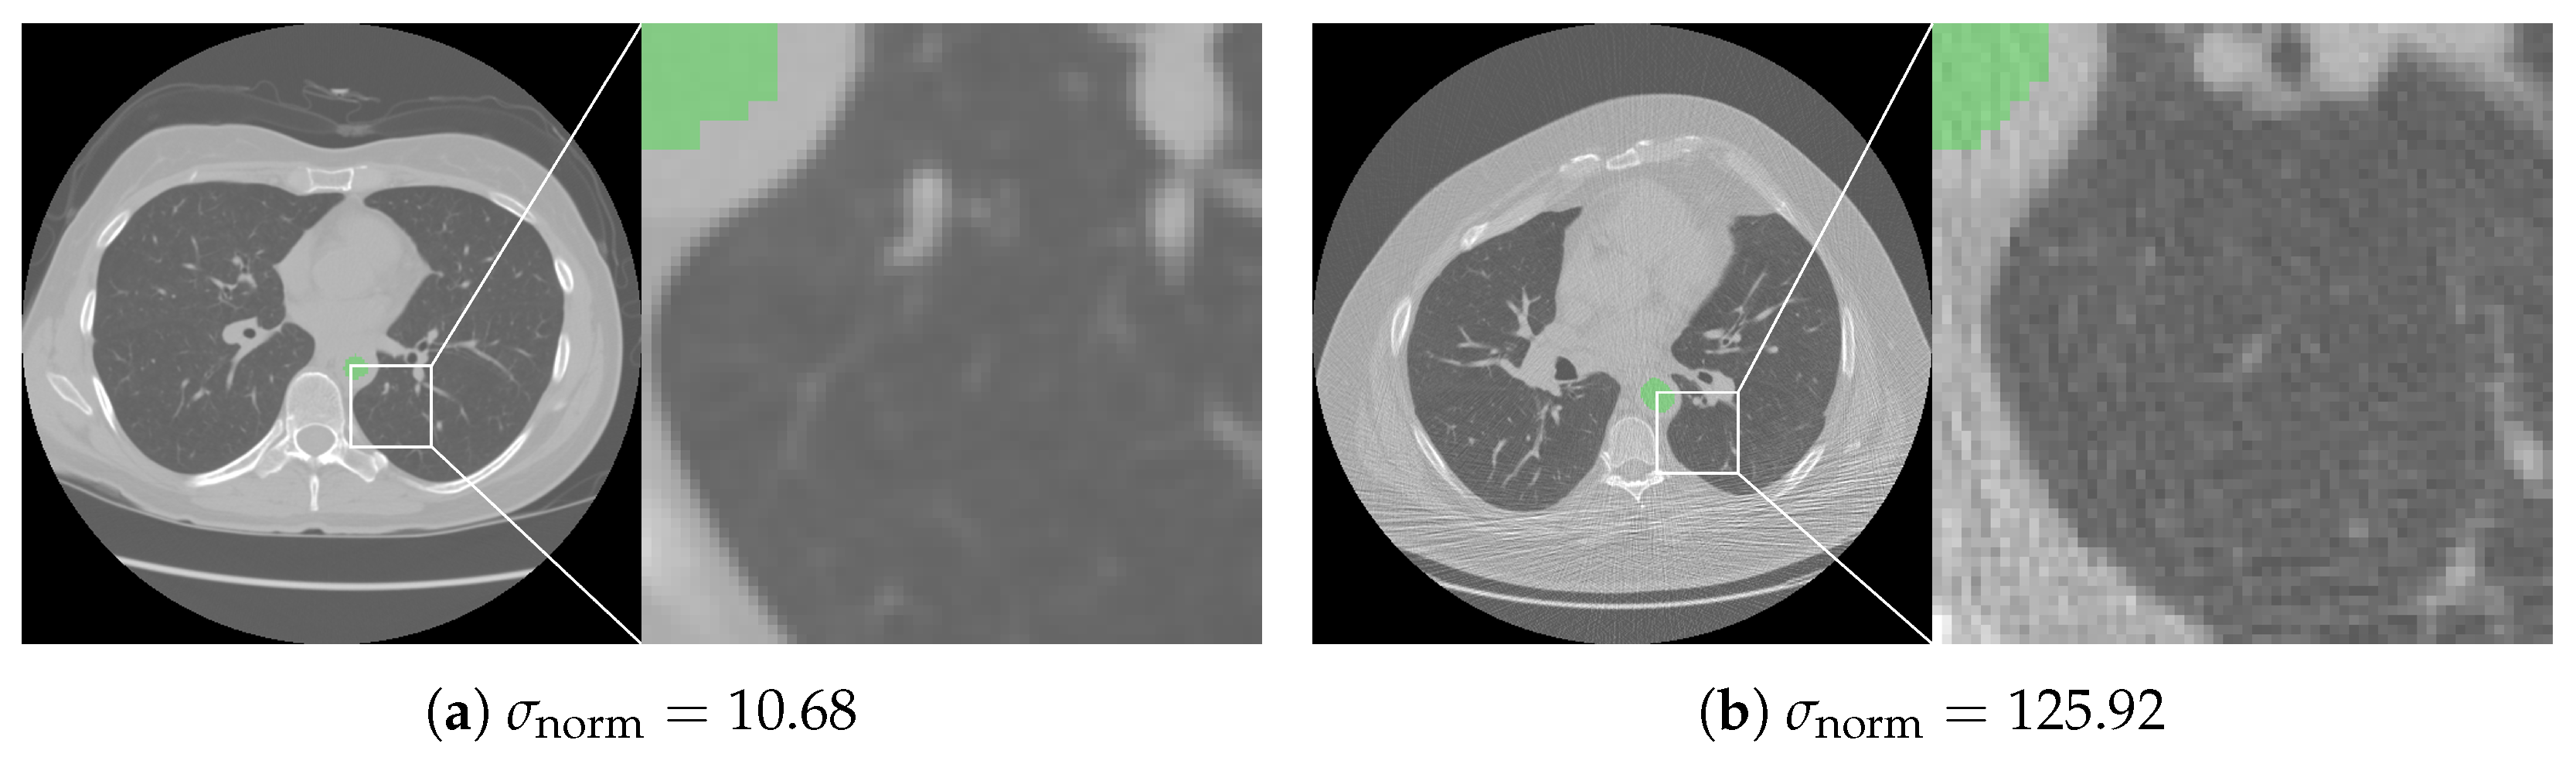

3.2. Noise Calculation